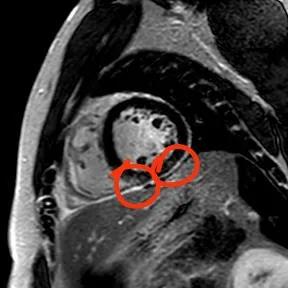

“快!做磁共振觀察心肌有無受損及程度。”影像診療中心陳寶瑩副主任為小燁進(jìn)行心臟磁共振平掃及增強(qiáng)掃描。結(jié)果提示:患者有急性心肌損傷,考慮心肌梗死。結(jié)果驗(yàn)證了小燁的心肌大片區(qū)失活。